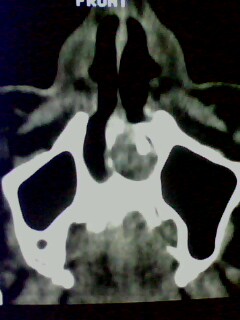

以下是引用随光逐影在2009-5-20 19:22:00的发言:[br]1)考虑左上颌骨近中线区含牙囊肿。2)鼻中隔右突偏曲。3)双侧下鼻甲肥大。